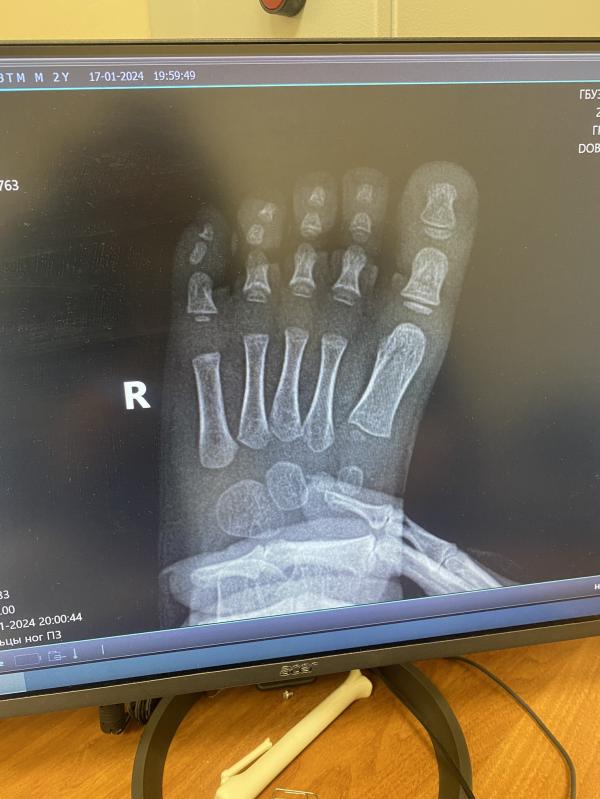

Есть ли тут кто разбирается в рентгене? У сына опух мизинец и красный весь, горячий. В травмпункте сказали ушиб. Я сомневаюсь((

Нет перелома.